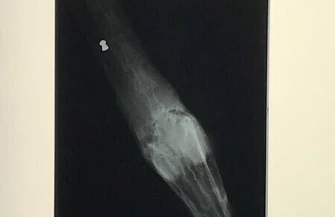

Postrzelony łabędź został znaleziony na tafli lodu na jeziorze Bugaj w Piotrkowie. Straż Miejska przewiozła ranne zwierzę do lecznicy w Sulejowie, gdzie zajął się nim specjalista - Rana zlokalizowana jest na szyi, natomiast sam śrut przemieścił się w okolicę trzeciego kręgu szyjnego. Udało nam się usunąć śrut i całkowicie zaszyliśmy ranę. Obecnie łabędź jest pod wpływem antybiotyku i jego stan jest stabilny - mówił Bartłomiej Kacprzyk, lekarz weterynarii z przychodzi w Sulejowie.